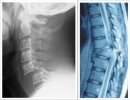

「iPS細胞を用いた脊髄損傷の再生医療」

画像2: https://www.atpress.ne.jp/releases/398623/LL_img_398623_3.jpg